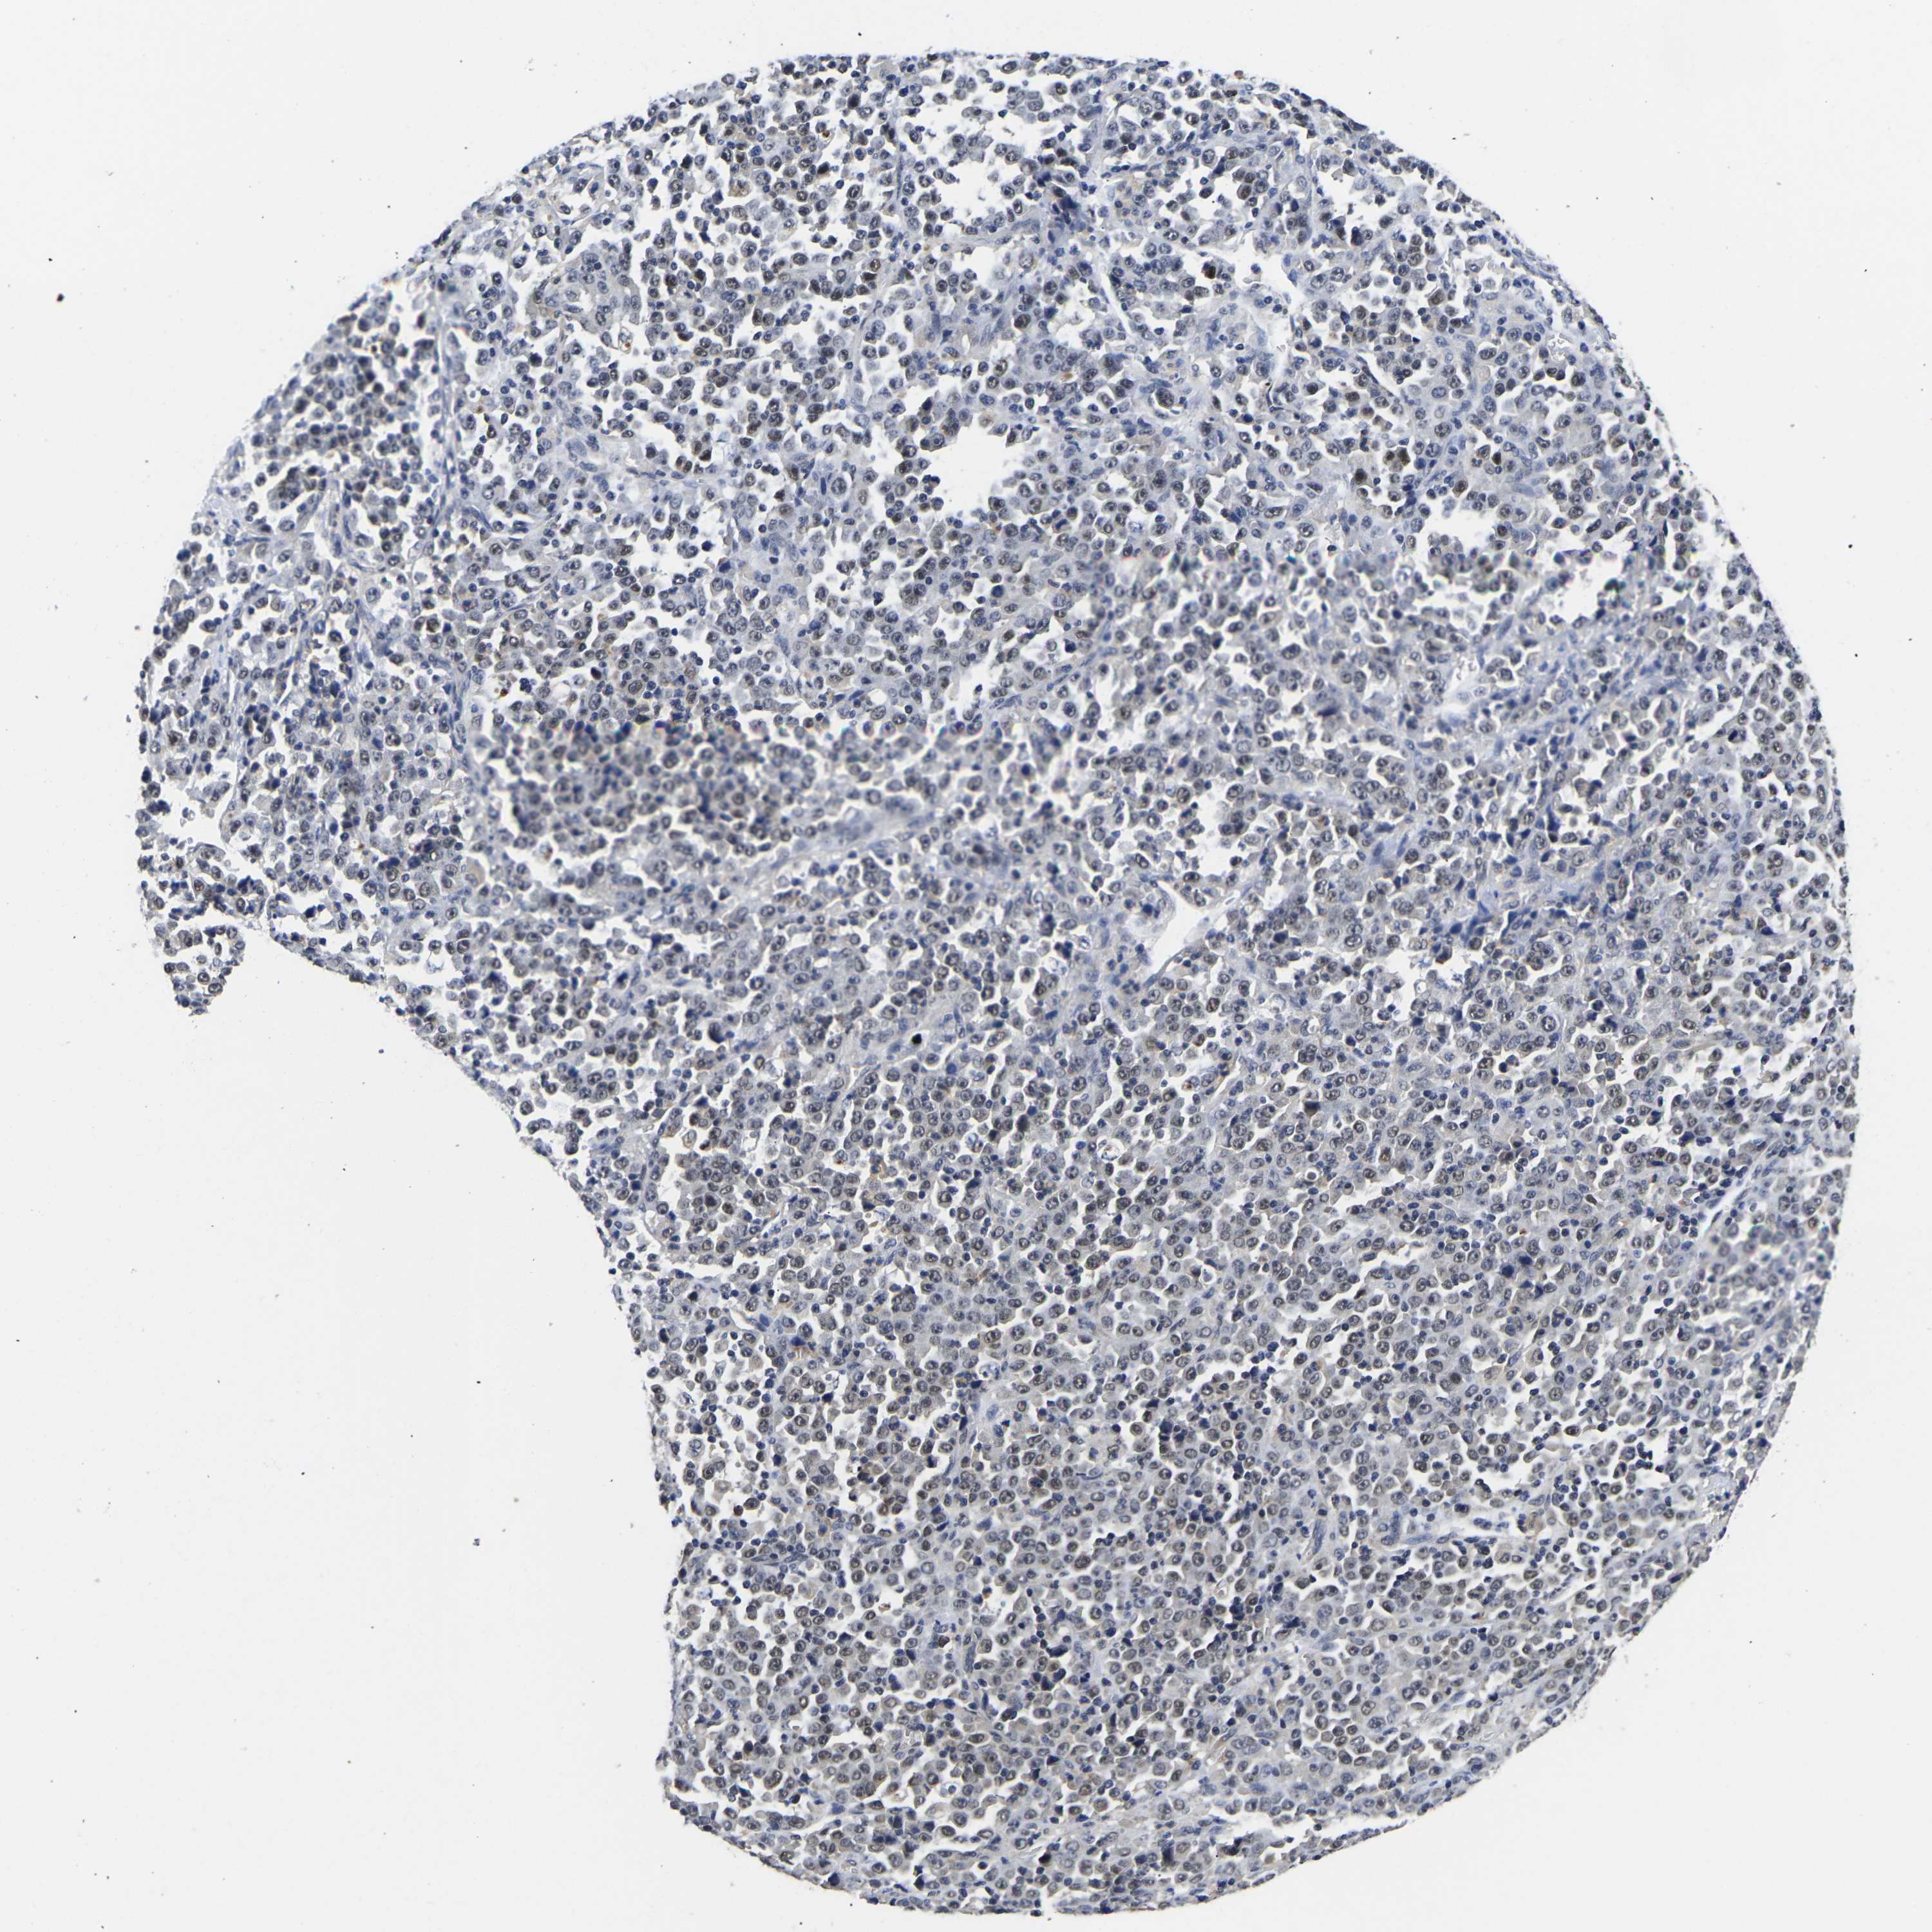

STOMACH CANCER - Protein expressioni

A mouse-over function shows sample information and annotation data. Click on an image to view it in a full screen mode. Samples can be filtered based on level of antibody staining by selecting one or several of the following categories: high, medium, low and not detected. The assay and annotation is described here.

Antibody stainingi

Antibody staining in the annotated cell types in the current human tissue is reported as not detected, low, medium, or high, based on conventional immunohistochemistry profiling in selected tissues. This score is based on the combination of the staining intensity and fraction of stained cells.

Each image is clickable and will lead to virtual microscopy that enables deeper exploration of all samples and also displays staining intensity scores, fraction scores and subcellular localization as well as patient and tissue information for each sample.

Antibody HPA020352

Staining

High

Medium

Low

Not detected

Intensity

Strong

Moderate

Weak

Negative

Quantity

>75%

75%-25%

<25%

None

Location

Nuclear

Cytoplasmic/membranous

Cytoplasmic/membranous,nuclear

Adenocarcinoma, NOS